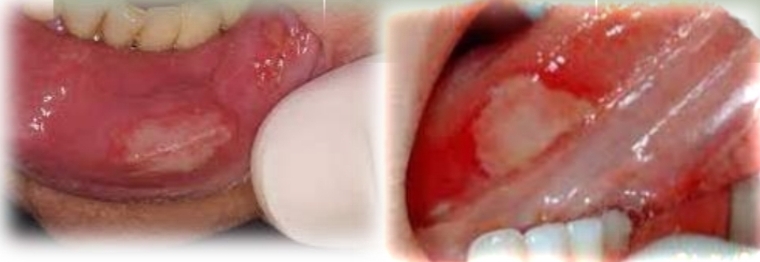

Single (usually), large ulcer, variable shape and irregular margins. Shallow or deep

Painful

First and second decade

No gender bias

Found on:

Lateral tongue, Buccal mucosa, lips and gingiva, ventral tongue

Ask: Recent injury to site?

Traumatic ulcer

Most common oral ulcer

May indicate:

Child abuse

Neurologic impairment

Factitial injuries when peristent and recurrent

Treatment - Typically heals in 1-3 weeks. Symptomatic relief, eliminate cause. Factitial ulcers are diagnostic problem. May heal with scarring.

DD - Apthous ulcer, Mucosal burn Secondary herpetic ulcer, Contact allergy